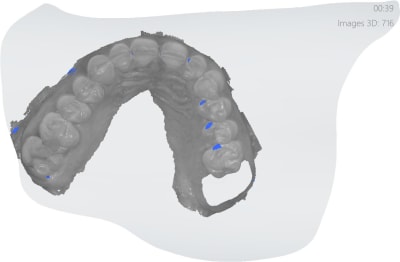

Oui des empreintes turbo. Préprep le temps que l'anesthésie de de 27 et 47 prennent pour les endos. Pour l'empreinte des préparations c'est 15 secondes. -))))